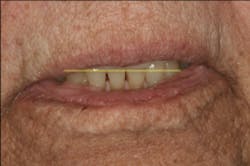

This clinical case began with a frustrated 75-year-old patient, who, after many years of failed attempts to repair the functional problem, came to the realization that a different solution was in order. The existing problem of an upper removable precision attachment partial denture was addressed first. The issue at hand was that the partial denture was perforated at the precision attachments, with the upper left side being more significant compared to the right side (figures 1–5). As a result, retention was adequate on the right side, but limited on the left. The patient was also concerned about esthetics, but needed a solution that kept a restricted budget in mind.

At rest or repose, ideally 1 mm to 3 mm of incisal edge is revealed. Often, aging causes the upper lip to drop, which reveals less than the 1 mm to 3 mm of incisal edge. (4) This patient does show some reveal, as illustrated in Figure 13, but at her age, none is expected to be seen. However, to confirm this, the “E” smile photo was used. This photo illustrates where the incisal edge falls between the upper and lower lips. Figure 14 illustrates how to use this photograph to help determine the vertical position of the incisal edge. Ideally, the incisal edge should be somewhere between 50% and 70% of the distance between the upper and lower lip. (5)